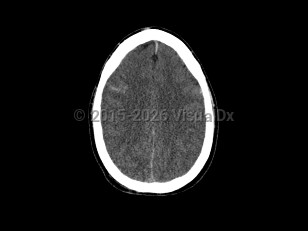

Cerebral edemaCerebral edema